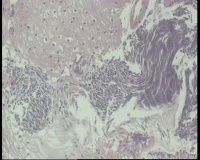

镜下见鳞状上皮大部分如(图1) ,仅局灶鳞状上皮异型(图2-4),细胞似牵拉变形,部分腺腔内见异型细胞团,这些细胞跟LEEP刀手术电凝有关系吗?这个怎么报?累腺明显,上皮图1怎么报?能报CINII—III累及腺体吗?还是宫颈高级别鳞状上皮内病变累及腺体

图1

CIN2-3累腺,有机械损伤,要按1-12点分别报告,要报告内外切缘情况。